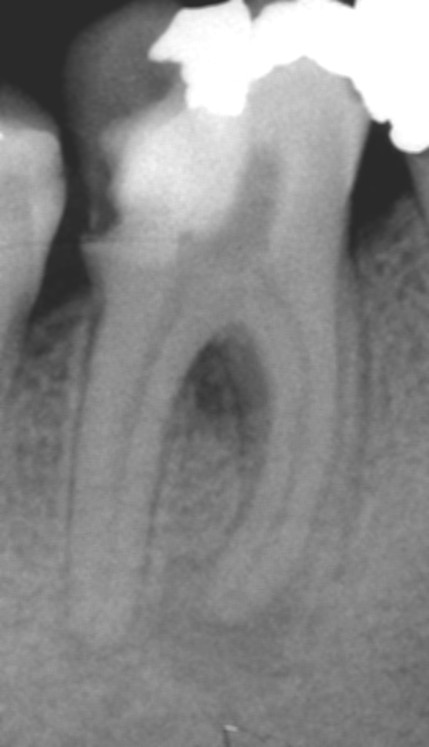

Apertura della corona fino ad arrivare alla camera pulpare (tale trattamento viene eseguito tramite anestesia locale). Si rimuove la polpa e si cercano i canali radicolari del dente, una volta trovati si estirpano i nervi. Si allargano e si puliscono i canali del dente, (tramite strumenti al Nichel titanio o strumenti manuali) prendendo anticipatamente le misure dei canali (per non uscire oltre apice). Si disinfettano i canali e si eseguono vari lavaggi tra un passaggio e un altro per elimininare il fango dentinale. Il medico a questo punto verifica la possibilità di chiudere definivamente i canali o lasciare il dente in prova, inserirendo nei canali un disinfettante e eseguendo una chiusura provvisoria. Al momento di chiudere il dente definivamente, questo viene preparato rieseguendo le misure dei canali da chiudere ed usando per la stessa lunghezza del canale, un cono di guttaperga del diametro necessario. Si scalda il cono in guttaperga e si inserisce nel canale. Durante il trattamento endodondico vengono effettuati una serie di esami radiografici per verificare i risultati, le lunghezze, la forma dei canali.

L'esame radiografico, fondamentale per porre diagnosi in odontoiatria, in endodonzia è irrinunciabile perché è l'unico strumento che ci permette di "vedere" all'interno della radice del dente, è quindi molto importante la possibilità di effettuare lastre con apparecchiature digitali che emettono un quarto della dose di raggi emessa da un radiografico tradizionale e che permettono di conservare la radiografia endorale in una cartella informatica del paziente senza possibili alterazioni nel tempo.